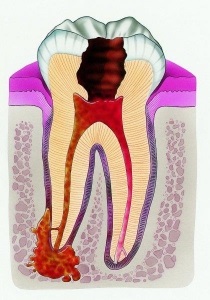

Tehát, periodontitis egy nagyon kellemetlen betegség üreg gyulladásos száj, vagy inkább kötőszöveti struktúrák a fogat körülvevő (periodontális). A fogorvosok azt mondják, hogy a harmadik részt orvoslátogatásonként gyermekek társul tejfogak fogszuvasodás és a fogágy. Ahhoz, hogy megértsük, hogyan és mit kell kezelni ezt a patológia, az orvosok azt sugallják, hogy megértsék a lényegét a betegség.

• Fertőzés. Ez a típus egyike a leggyakoribb. Az ok a gyulladás a legtöbb esetben, ez lesz a kórokozó mikroflóra, amely behatol a gyökérkezelés, a lyuk a tetején a fogat. Azt is meg kell jegyezni, hogy egy másik módja a fertőzés lehet egy él vagy marginális periodontitis. Amikor bekövetkezik behatolását mikroflóra keresztül a gingivális zsebében vagy jelenlétében periodontitis egy szomszédos fog. Különösen akkor, ha ennek eredményeként a ciszta találtak a felmérés, hozzájárulva a penetráció fertőzés a kötőszövet a fogat körülvevő.

• Akut apikális periodontitis pépet az eredete. Ha ez tisztán látható a klinikai képet, és viszonylag könnyen telepíthető okok patológia.

• Az apikális periodontitis, krónikus lefolyású. Diagnózis jelenlétét mutatja granulomák, ami jelzi a hosszú távú a folyamat során.

• Periapicalis abstsesss fistula. Ebben az esetben beszélünk a betegség, bonyolítja mély szöveti károsodás. A szakértők azonosítani többféle periodontitis: alveolaris, dentoalveolar vagy periodontális tályog a pépet etiológiájú.

• Periapicalis fisztulaképződés abstsessbez. Fogorvosok itt is a fogászati tályog, Periapicalis tályog nélkül sipoly, tályog dentoalveolar, periodontális tályog pép az eredete.

• A gyökér fonálféreg bezárja ezt az osztályozást. Ez lehet az apikális (apikális) és az oldalsó.

• undertreated vagy nem időben gyógyítható pépet. Az eredmény egy olyan üreg tele kórokozó mikroflóra. A mikrobák adja meg a kötőszövet a fogat körülvevő struktúra és gyulladást okoznak.

• A nem megfelelően beszerelt tömítések gyökérkezelés. Még egy kis űrt orvosához okozhat a fejlesztési kórokozó szervezetek a fertőzés továbbterjedését.

A differenciál-diagnózis kiemelkedő radiográfiai, amely a legteljesebb képet a feltétele a fogak, és a jelenléte zsebek, ciszták vagy elégtelenül lezárt minőségileg csatornák.

Egy X-ray lesz jól látható sötét folt lokalizált csúcsán a gyökér. Hogy ez a legfontosabb diagnosztikai funkció, amely egyértelműen azonosítja az oka a kóros folyamatot. Ugyanilyen fontos a sipoly, valamint bőrpír a fogíny területe a sérült fogat.